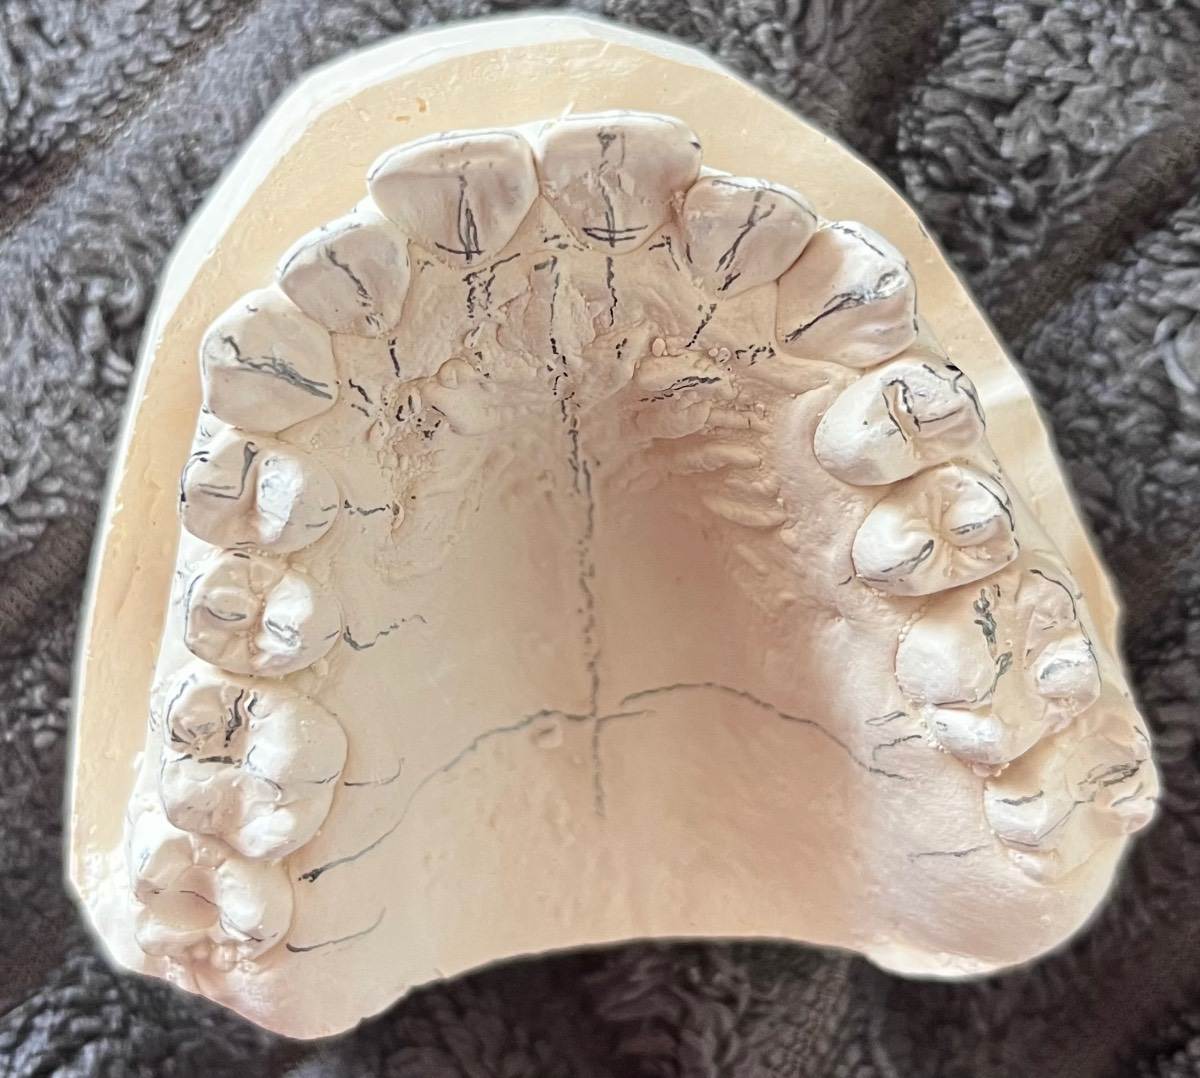

Мне 17 лет, я хочу поставить брекеты. У меня на нижней челюсти скученность зубов, на верхней протрузия (зубы передние отклонены вперед на 2-3 градуса). Прикус в норме. Удаляла 1 зуб мудрости внизу, 2 месяца назад, потому что очень давил на зубной ряд, и вот сейчас решила заняться брекетами. Пошла к одному ортодонту - сказал что наверху никакие удалять не надо, они никак не мешают, только нижний зуб мудрости, второй удалить, и то позже. Прихожу к другому ортодонту, говорит что надо удалять 5-ые зубы — 2 сверху, 2 снизу, ибо по другому не исправить ситуацию, без удаления им не будет места и они из кости вылезут просто.. очень нужен совет, какие зубы удалять? Фото снимков и слепков нижеIMG_5334.jpeg.b29acf03abb1dd3861d2f5c50d9defed.jpegIMG_5337.jpeg.05a95352e4a6439f90f8c35cb28336e8.jpegIMG_5338.jpeg.863efa671750d73ce517a3979f6646cb.jpegIMG_5336.jpeg.af01d9033016196d4046949a804ccd63.jpegIMG_5335.jpeg.0f2aaff927e30a409e8f5bb173a1dede.jpeg